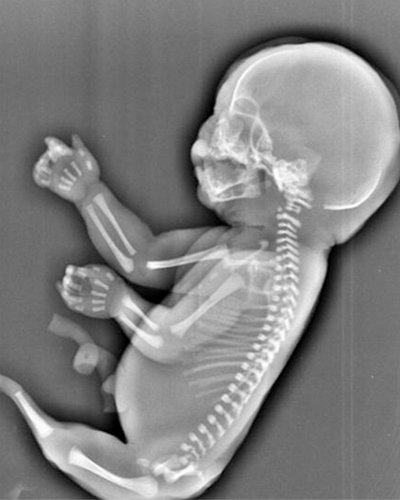

Sự việc bất thường xảy ra tại thành phố Nghi Xương, Trung Quốc. Người phụ nữ mang tên Wu được bác sĩ chẩn đoán cô mang thai một người cá. Cô đã bị sốc khi nghe tin này nhưng đã dũng cảm quyết định bỏ đi cái thai này.

Người cá nghĩa là thay vì phát triển như những đứa trẻ bình thường khác, hai chân của thai nhi 6 tháng tuổi này lại dính liền với nhau trông không khác là bao so với đuôi của người cá.

Hình ảnh siêu âm cũng cho thấy thai nhi không có bàng quang và hai lá gan phát triển không đồng đều.

Các bác sĩ ở thành phố Nghi Xương, Trung Quốc cho rằng thai nhi trong bụng của cô Wu mắc 'hội chứng người cá'.

Đây là hội chứng rất hiểm gặp với tỷ lệ mắc bệnh rất nhỏ, chỉ 1/100.000 thai nhi và nguyên nhân gây ra căn bệnh này cho đến nay vẫn là một bí ẩn trong y học.